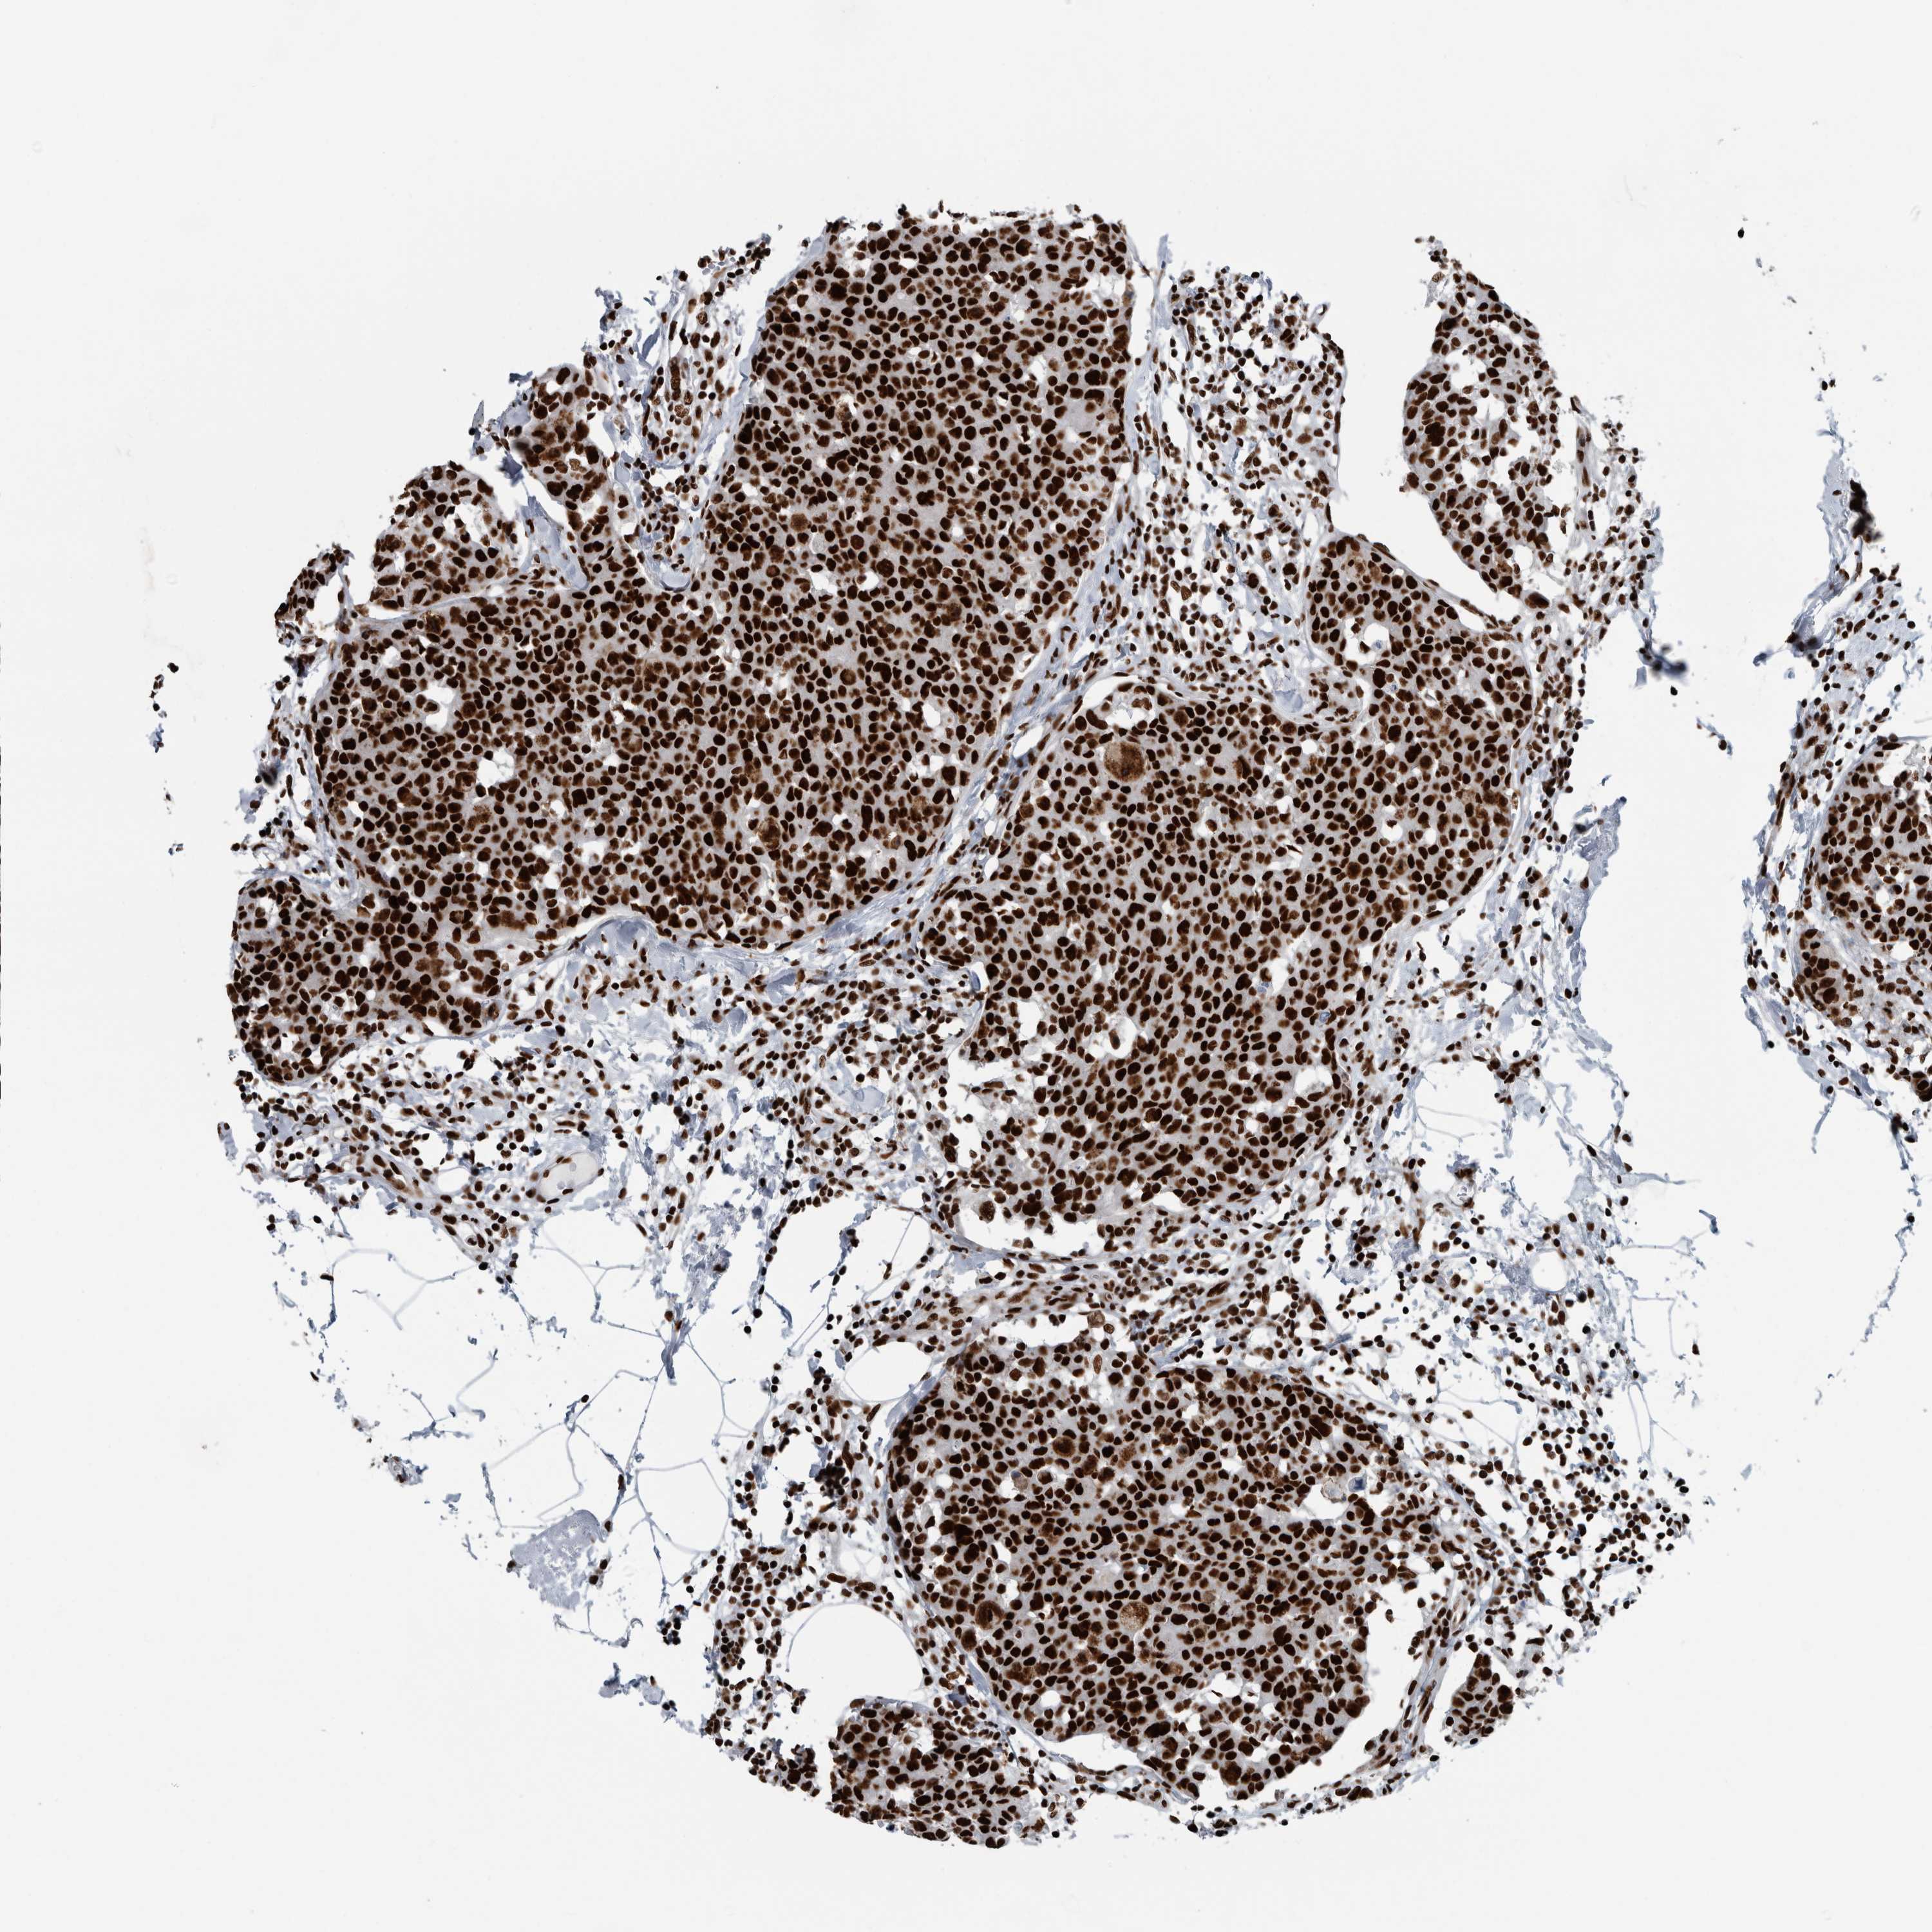

CANCER BREAST CANCER Show tissue menu

BRCA TCGA BRCA VALIDATION PROTEIN EXPRESSION

ANTIBODIES

AND

VALIDATION